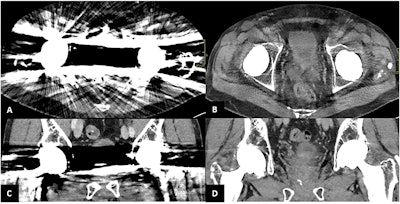

Patient with bilateral hip prosthesis undergoing PCCT scan. Axial and coronal views (A, C) show severe metal artifacts. Axial and coronal reconstructions after energy filtering (B, D) demonstrate a significant reduction in metal artifacts.Bruno, Palmisano et al; Insights into Imaging